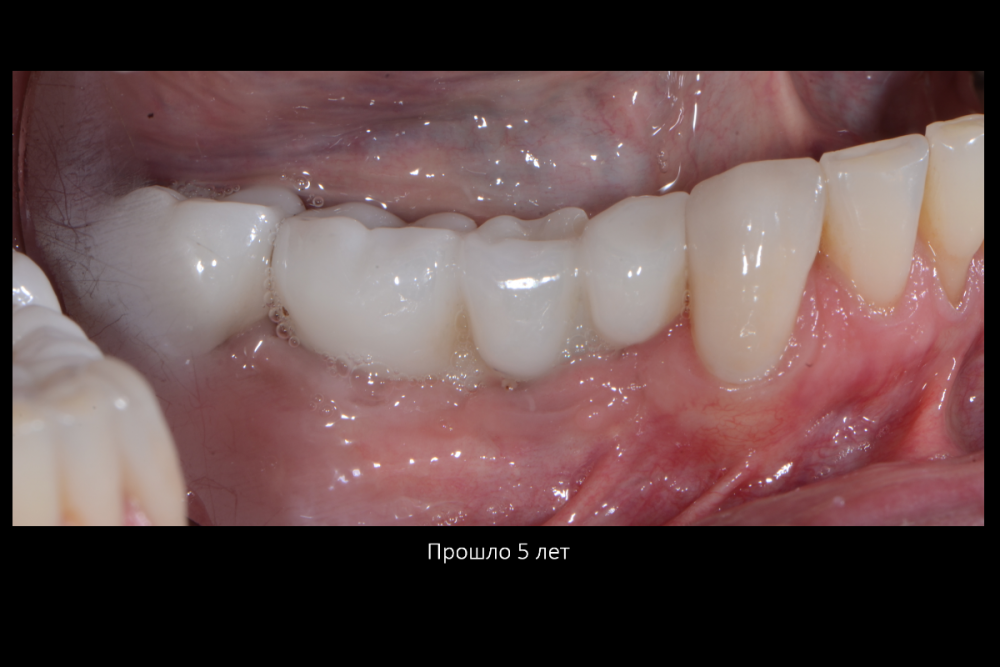

Карен Аванесов Опубликовано 11 февраля, 2022 Поделиться Опубликовано 11 февраля, 2022 все на слайдах. 2 Ссылка на комментарий

Карен Аванесов Опубликовано 11 февраля, 2022 Автор Поделиться Опубликовано 11 февраля, 2022 10 минут назад, Дмитрий Л. сказал: Прокомментируете? Имею опыт по таким методам "присыпки", результаты хорошие, но не впечатли Ссылка на комментарий

Карен Аванесов Опубликовано 12 февраля, 2022 Автор Поделиться Опубликовано 12 февраля, 2022 15 часов назад, АнтонТЛТ сказал: Я при таких сюрпризах делаю мобилизацию язычного лоскута, вестибулярный не мобилизирую, фдм вторым этапом. Что на 4 слайде справа? Делал и так ка ты написал. коллаген 15 часов назад, Irouil сказал: Кажется, там какой-то алографт на который сверху подсыпан ксено можно ли проследить вывод из работы, что лучше «без», чем «с»? Именно! и не только. Полезно смотреть старые работы. только не все пациенты исправно приходят Ссылка на комментарий

Карен Аванесов Опубликовано 15 февраля, 2022 Автор Поделиться Опубликовано 15 февраля, 2022 13.02.2022 в 22:56, Fin сказал: Карен. Подскажите пожалуйста. Правильно ли я понял, что в на данный момент в такой ситуации (оголение импланта с вестибулярной стороны на половину) Вы бы обошлись просто установкой импланта + ССТ вестибулярно? Да, именно так. 14.02.2022 в 10:33, Bier сказал: от подобной присыпки толку обычно нет. Олег, помнишь аник "темно здесь..." Вот только не начинай про полужесткие сосиски)))) Но ты прав или делпать по отработанной технологии или никак 1 Ссылка на комментарий